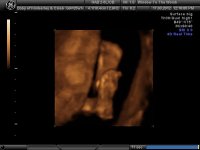

Hope everyone else is ok, and the photos are lovely Kim, and Luis (think I have already said so.. but wanted to say again incase!)

Very cute!